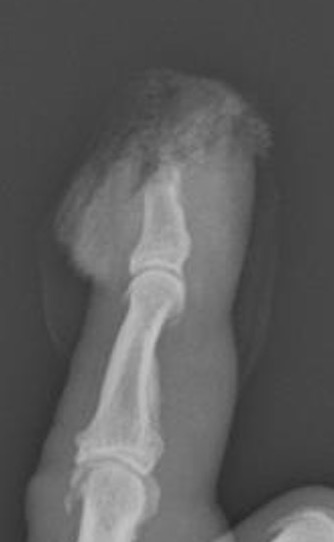

Detipping

Definition

Distal to insertion of flexor and extensor tendons

Tissue involved

Pulp only

Nail bed

Bone